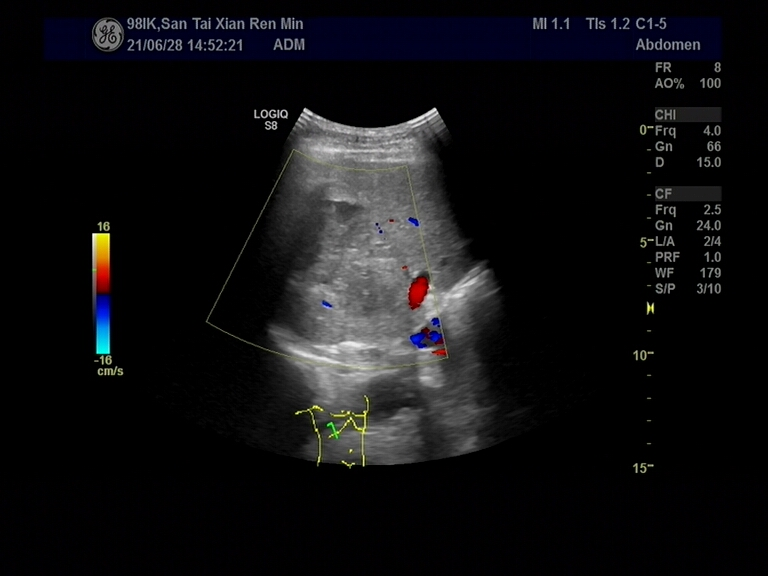

小中大近日,我院超声科成功为一位老年男性成功进行肝组织穿刺活检术,此次手术的顺利开展,是科室诊断技术提升实现的再一次突破,标志着科室在肝脏疑难疾病诊断领域迈上了新台阶。

一位老年男性因无明显诱因反复咯血2+月来到我院就诊,患者身体十分消瘦,为明确病变性质及来源,尽早采取最佳的治疗方案,缓解患者症状,提高生活质量,为研究寻找最佳穿刺路径,减少出血,经我院临床多学科联合会诊,经过周密准备,决定为患者行超声引导下经皮肝脏穿刺活检术。

术中,介入组医生们仔细操作,寻找最佳穿刺路径,减少术中出血,经成功取得标本,顺利完成我院首例肝脏穿刺活检术。术后病理结果及免疫组化提示为恶性,目前该患者正在进行进一步的治疗。

经皮肝脏穿刺活检:是指在超声引导下,经皮用穿刺针吸取肝脏组织进行的病理检查,是目前诊断肝脏疾病科学、简便、有效的方法之一;遵循循证医学原理,可以早期、快速、准确的诊断肝脏疾病。此法对于肝炎﹑黄疸、酒精性肝损害﹑脂肪肝﹑不明原因肝酶升高或发热、肝癌等肝实质病变的诊断均有帮助。